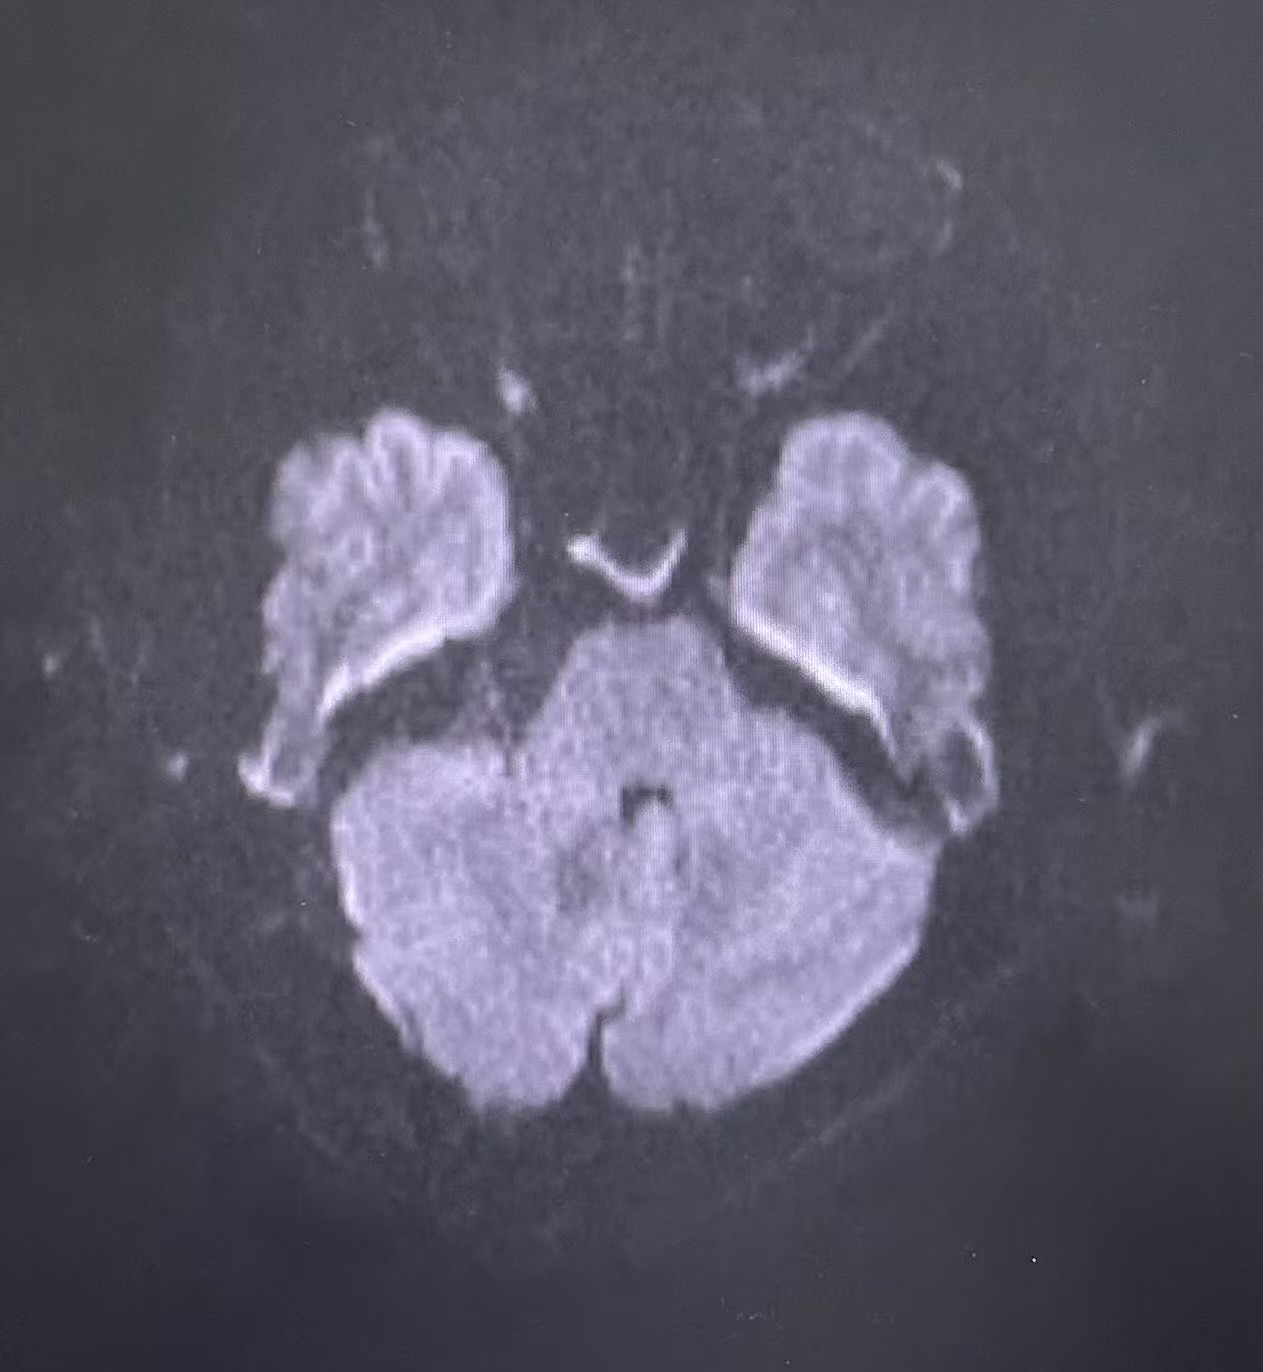

患者术后核磁共振影像

术后,在神经外科护理团队的精心照料下,贾女士恢复顺利。最让她开心的是,困扰她两年的“闪电样”剧痛彻底消失了,且没有出现面瘫、听力下降、偏瘫、吞咽困难等神经功能损伤并发症。出院后,贾女士回归了正常生活。经过3月余的定期随访复查,头颅MRI显示肿瘤无复发,贾女士的生活质量得到了显著提高。